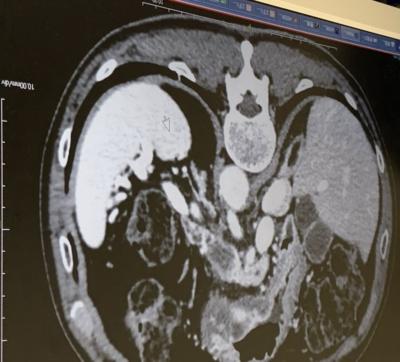

齢77血糖値異常?!癌が見つかった、即外科削除!

- travelの友達も、定期検査で予防と最低限の治療を!原稿寿命だから、楽しめる国内外の散策ですから! CORONA禍に良く見つかった私の癌細胞!術前の造影画像や......もっと見る(写真16枚)

見つかっちゃった!ガン細胞、オペ入院!

- まさか!CORONA禍に癌の早期発見!齢77 開腹手術へのアプローチ!終いの初めての入院、生かされて!メディカル機器の進化!久しぶりの聴診器!術後回復へのチャレ......もっと見る(写真46枚)